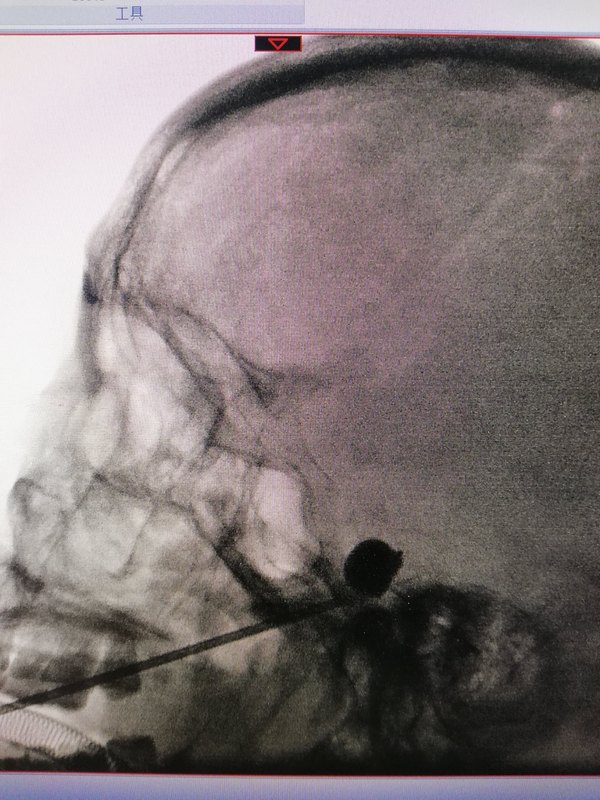

三叉神經(jīng)痛往往疼痛劇烈,且反復(fù)發(fā)作,被稱為‘’天下第一痛‘’。 疼痛發(fā)生后患者首先采取藥物治療,如卡馬西平及中藥等,一般可起到緩解疼痛的作用。但時(shí)間久了,一部分患者出現(xiàn)藥物沒(méi)效果了,或出現(xiàn)比較重的藥物不良反應(yīng),這種情況就要采取外科手術(shù)一類的方法。 這些方法主要包括顯微血管減壓術(shù)、射頻熱凝術(shù)、球囊壓迫術(shù)。那么采取哪種方法最為合適呢?除了這幾種方法的具體特點(diǎn)外,還要結(jié)合患者的身體狀況、年齡、治療經(jīng)過(guò)等因素來(lái)考慮。 顯微血管減壓術(shù)從發(fā)病機(jī)理來(lái)講,可以通過(guò)顯微手術(shù)解除疼痛的根本原因,而且一般不會(huì)影響面部的感覺(jué),因此被認(rèn)為是首選的外科治療方法,多數(shù)情況下可以選擇。 但如果患者是年齡很大,身體比較衰弱,或者是已經(jīng)接受過(guò)血管減壓術(shù)或其他治療復(fù)發(fā)的,則可能選擇創(chuàng)傷更小的方法更為合適,球囊壓迫術(shù)對(duì)此種情況尤為合適。球囊壓迫術(shù)是僅進(jìn)行一次性穿刺就可完成的微創(chuàng)治療方法,具體做法是采取全麻,治療期間患者不會(huì)有疼痛感覺(jué),在口角旁邊扎入穿刺針,在DSA或CT等機(jī)器的引導(dǎo)定位下精準(zhǔn)到達(dá)三叉神經(jīng)半月節(jié),再導(dǎo)入球囊壓迫一到兩分鐘就可完成這個(gè)手術(shù)。 球囊壓迫術(shù)的止痛效果可以達(dá)到90%左右,患者的恢復(fù)很快,一般術(shù)后第二天就可出院了。和其他方法一樣,雖然也存在著一定程度復(fù)發(fā)的問(wèn)題,但其具有微創(chuàng)、治療期間無(wú)痛苦、起效快、恢復(fù)快、可重復(fù)等優(yōu)點(diǎn),不失為治療三叉神經(jīng)痛的一種較好方法。